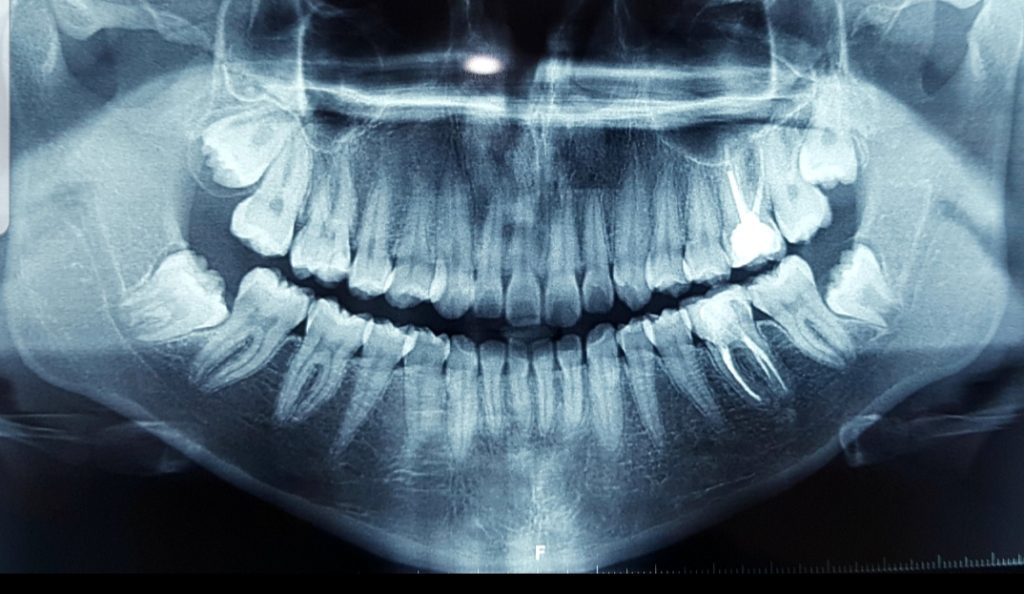

No puedes saber con exactitud si te está saliendo la muela del juicio, pero si visitas al dentista cada seis meses para que te haga una limpieza y un control, este puede supervisar el crecimiento y la aparición de las muelas de juicio. Las radiografías dentales regulares pueden revelar una muela de juicio retenida antes de que se manifieste algún síntoma.

Algunas personas tienen muelas de juicio que salen sin ningún problema y se alinean con los otros dientes, detrás de los segundos molares. Sin embargo, en muchos casos, la boca no tiene suficiente espacio para que los terceros molares crezcan con normalidad. De esta manera, los terceros molares quedan atrapados (retenidos).

Una muela de juicio retenida puede aparecer parcialmente, de modo que se ve parte de la corona, o pueden no atravesar nunca la encía.